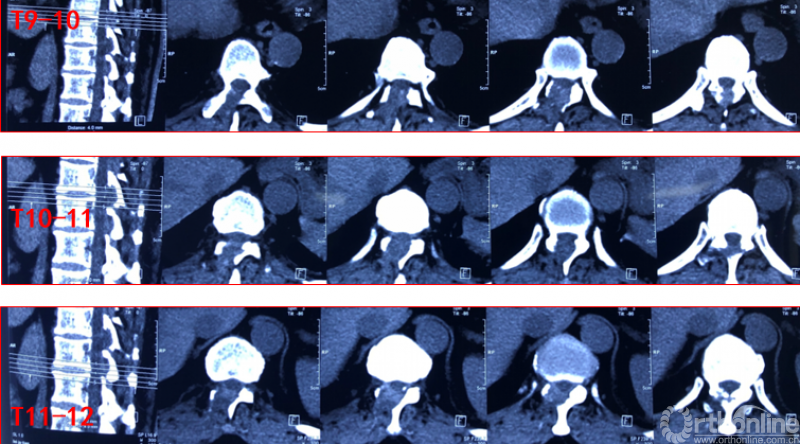

术前资料

术前诊断及评分

JOA评分:5分

ASIA等级:C级

诊断:

1:胸椎间盘突出伴钙化下肢不全瘫